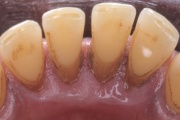

Krooniline parodontiit

Krooniline parodontiit on mikroobide poolt põhjustatud hammaste tugikudede põletik, mille tulemusena tekib progresseeruv alveolaarluu (nähtav röntgenograamil) ja periodontaalligamendi destruktsioon, igemetaskute moodustumine, igeme retsessioon või mõlemad kahjustused kombineeritult. Loe edasi »

- igemed veritsevad (19)

- igemed punetavad (21)

- ige on paistes (mädapunn)

- igemed on tursunud/vohavad (17)

- igemepiir on taandunud (3)

- igemepealne hambakivi (5)

- igemealune hambakivi (4)